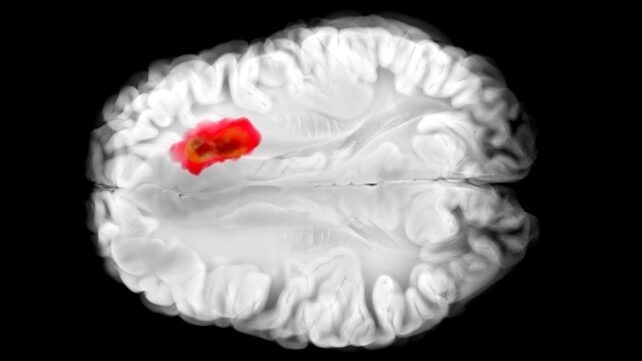

La hidralazina se ha utilizado para tratar la presión arterial alta durante décadas, aunque nunca ha quedado claro exactamente cómo funciona. Ahora un nuevo estudio responde a algunas preguntas clave sobre este medicamento, y añade un vínculo intrigante con el cáncer cerebral. Al analizar de cerca los efectos de la hidralazina en células humanas y de ratón, un equipo de la Universidad de Pensilvania descubrió que bloquea una enzima llamada 2-aminoethanethiol dioxygenase (ADO). Esa misma enzima, por cierto, se cree que desempeña un papel en glioblastoma agresivo. Este nuevo entendimiento de la hidralazina podría abrir camino a nuevos tratamientos contra el cáncer, así como mejorar la eficacia del fármaco para sus dianas actuales. Relacionado: La serotonina podría desempeñar un papel inesperado en el cáncer, descubren científicos. «Hydralazina es uno de los vasodilatadores más antiguos desarrollados, y sigue siendo un tratamiento de primera línea para la preeclampsia, un trastorno hipertensivo que representa entre el 5 y el 15 por ciento de las muertes maternas en todo el mundo», dice el médico e investigador Kyosuke Shishikura, de la Universidad de Pensilvania. «Provino de una era de 'pre-target' en el descubrimiento de fármacos, cuando los investigadores se basaban en lo que veían en los pacientes primero y solo después trataban de explicar la biología que hay detrás de ello». Los investigadores describen ADO como una «alarma» que alerta al cuerpo ante la caída de los niveles de oxígeno. Desencadena una cadena de reacciones, estrechando los vasos sanguíneos al destruir las llamadas proteínas RGS (acrónimo de Reguladores de la Señalización de Proteínas G). Estudios previos han mostrado que los tumores de glioblastoma suelen presentar altos niveles de ADO, aprovechándolo para producir un químico llamado hipotaurina, que ayuda a que las células cancerosas se diseminen, sobrevivan por más tiempo y toleren el estrés. Pero no se conocían inhibidores de ADO antes de este estudio. Hydralazina silencia efectivamente ADO, encontró el equipo: las proteínas RGS no son atacadas, los vasos sanguíneos no se contraen y la presión arterial cae. En experimentos con células de glioblastoma humano, la hidralazina detuvo el crecimiento tumoral al bloquear ADO. Es muy temprano: los efectos de la hidralazina aún deben evaluarse en personas con glioblastoma en ensayos clínicos, pero estos son hallazgos prometedores que podrían abrir un camino para controlar la propagación de estos tumores cerebrales notorios y difíciles de tratar. El mecanismo recién descubierto también explica por qué la hidralazina es un tratamiento eficaz para la preeclampsia, una condición de hipertensión en mujeres embarazadas. Eso significa que el fármaco puede ser mejor diseñado y personalizado para reducir efectos secundarios y mejorar resultados. «Comprender cómo funciona la hidralazina a nivel molecular ofrece un camino hacia tratamientos más seguros y selectivos para la hipertensión relacionada con el embarazo —posiblemente mejorando los resultados para las pacientes que están en mayor riesgo», dice Megan Matthews, de la Universidad de Pensilvania. Los descubrimientos aquí significan que se pueden desarrollar mejores fármacos tanto para la hipertensión como para el cáncer cerebral, equilibrando cuidadosamente la necesidad de atacar vías específicas en las células y minimizando el daño a las partes sanas del cuerpo. Y dado que la hidralazina ya se usa ampliamente, entender su mecanismo de acción da a los científicos una ventaja si quieren construir más tratamientos basados en este compuesto. Más adelante, podríamos eliminar una de las defensas clave del glioblastoma, sumando a los tratamientos ya en desarrollo. «Es raro que un fármaco cardiovascular antiguo termine enseñándonos algo nuevo sobre el cerebro», afirma Matthews, «pero eso es exactamente lo que esperamos encontrar más a menudo: conexiones inusuales que podrían significar nuevas soluciones». La investigación se publicó en Science Advances.

Los investigadores describen ADO como una «alarma» que alerta al cuerpo ante la caída de los niveles de oxígeno. Desencadena una cadena de reacciones, estrechando los vasos sanguíneos al destruir las llamadas proteínas RGS (reguladores de la señalización de proteínas G). Estudios previos han mostrado que los tumores de glioblastoma suelen presentar altos niveles de ADO, aprovechándolo para producir un químico llamado hipotaurina, que ayuda a que las células cancerosas se diseminen, sobrevivan por más tiempo y toleren el estrés. Pero no se conocían inhibidores de ADO antes de este estudio. Hydralazina silencia efectivamente ADO, encontró el equipo: las proteínas RGS no son atacadas, los vasos sanguíneos no se contraen y la presión arterial cae. En experimentos con células de glioblastoma humano, la hidralazina detuvo el crecimiento tumoral al bloquear ADO. Es muy temprano: los efectos de la hidralazina aún deben evaluarse en personas con glioblastoma en ensayos clínicos, pero estos son hallazgos prometedores que podrían abrir un camino para controlar la propagación de estos tumores cerebrales notorios y difíciles de tratar.